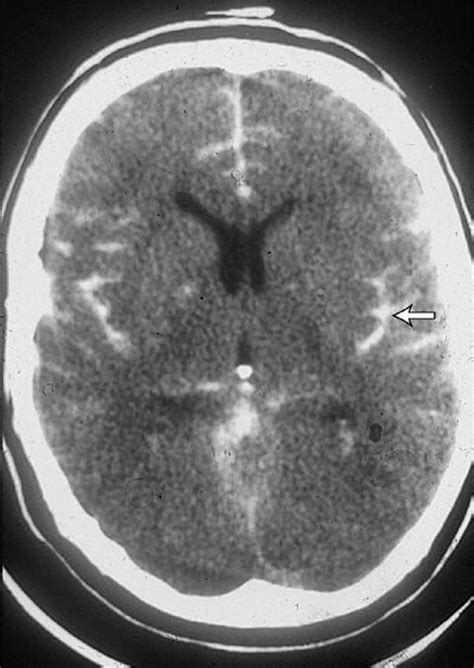

When blood leaks into the subarachnoid space, it appears as a bright, high-density (white) area on the scan, contrasting sharply with the darker, fluid-filled ventricles and brain tissue. The sensitivity of the scan is paramount; modern multidetector scanners are capable of detecting even very small amounts of subarachnoid blood. However, as time passes from the initial hemorrhage, the sensitivity of the scan decreases as the blood begins to dilute or break down.

• Interpretation by Radiologist: Careful examination for hyperdense areas in the sulci, cisterns, or fissures of the brain.

Despite the high sensitivity of the Subarachnoid Hemorrhage CT, there are instances where imaging can be deceptive. Small volumes of blood or specific anatomical locations can make interpretation difficult for the untrained eye. Moreover, in patients with severe anemia, the blood on a CT scan might appear less dense, making it harder to distinguish from the surrounding brain parenchyma. This phenomenon, known as the "isodense" sign, requires high-resolution imaging and expert clinical correlation.